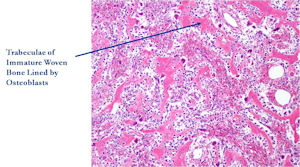

- Consists of well vascularized connective tissue stroma with interconnecting trabeculae of osteoid and woven bone

Microscopic Pathology

- Interlacing network of bone trabeculae in a loose fibrovascular stroma

- Prominent vessels

- Osteoblasts are plump, active, scattered mitotic figures

- Osteoblasts line up around periphery of trabeculae (Osteoblastic Rimming)